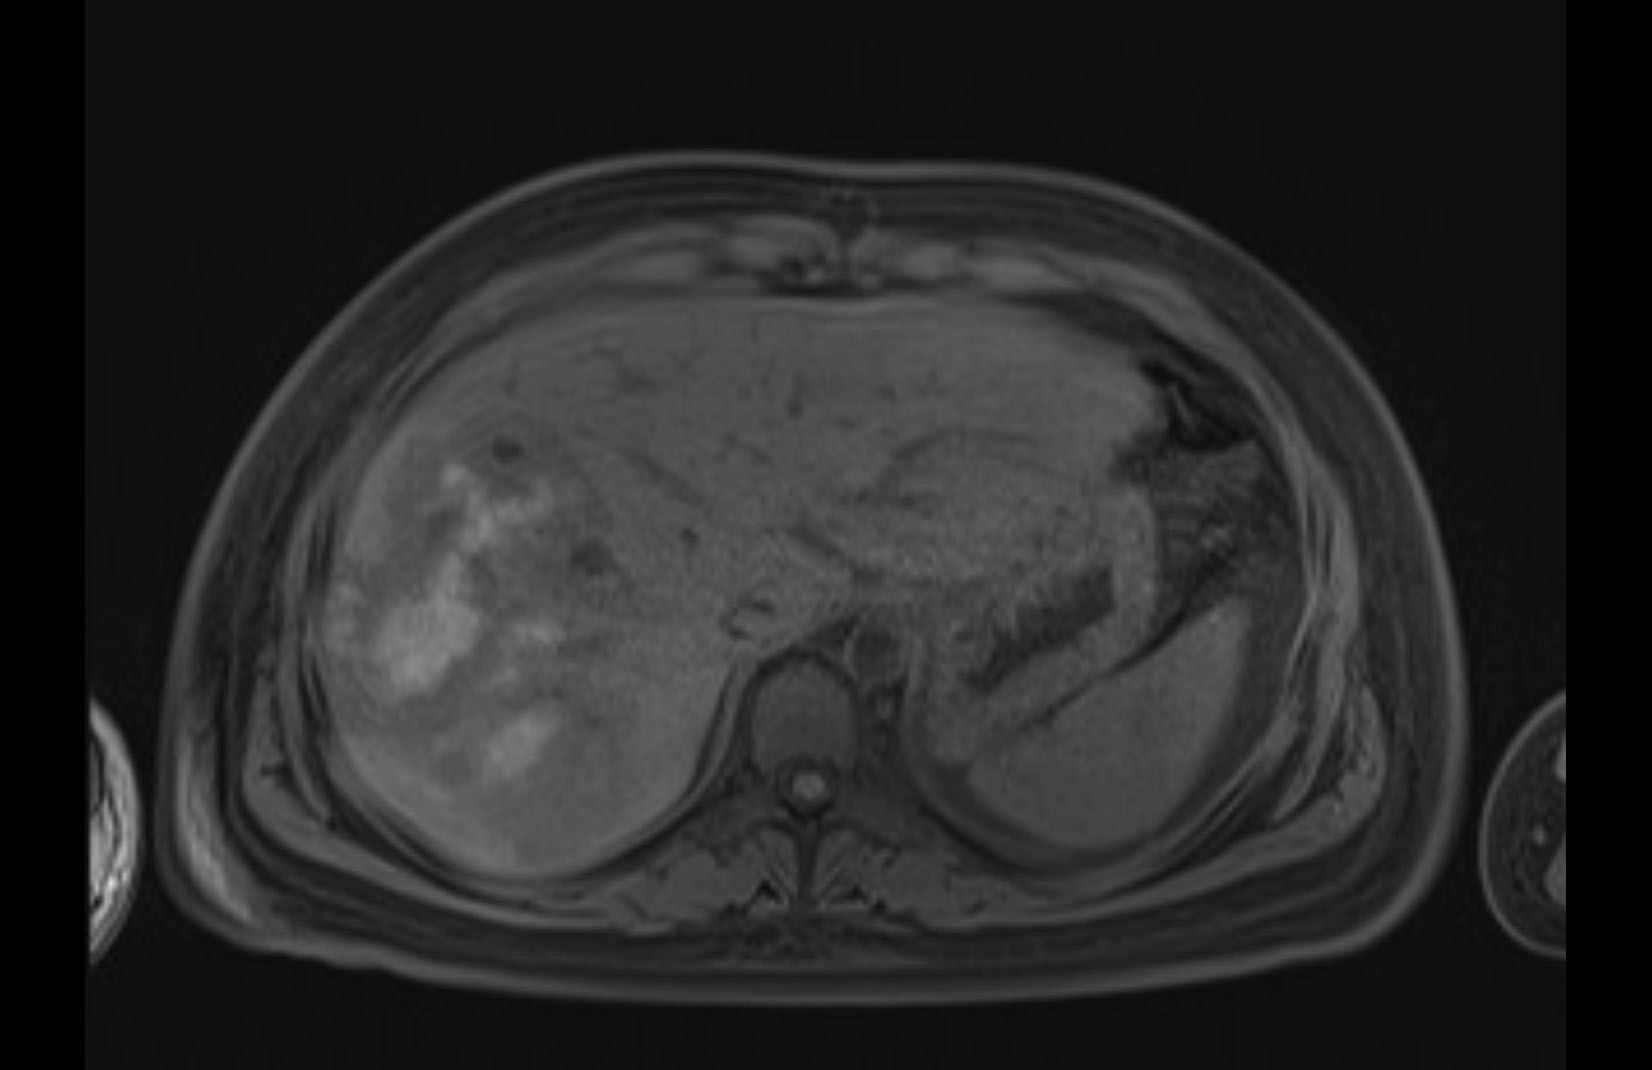

Imaging Analysis

Look through the patient's CT scan to identify any areas of concern for the necessary procedure.

MRI T2

Based on initial findings, which issue(s) would you be most concerned about?